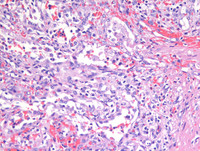

Figure 1: H&E images

Low power photomicrographs reveal a well demarcated tumor within the red pulp and uninvolved spleen at the periphery. Tumor shows proliferation of anastomosing vascular channels interspersed with dilated vascular and cyst like spaces.

Figure 2: H&E images

As noted on medium power photomicrograph (Image on the left), vascular channels have irregular lumina with focal papillary projections. High power photomicrograph (Image on the right) reveals vascular channels that are lined by tall and plump, bland-looking cells, some of which are seen projecting and sloughing into the lumina. Cytologic atypia is not evident.